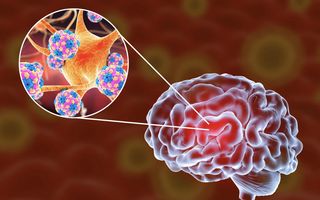

Ai bị cúm nên chú ý điều này

(NLĐO) - Hiện nay, thời tiết giao mùa tạo điều kiện thuận lợi cho virus cúm phát triển và lây lan nhanh chóng.